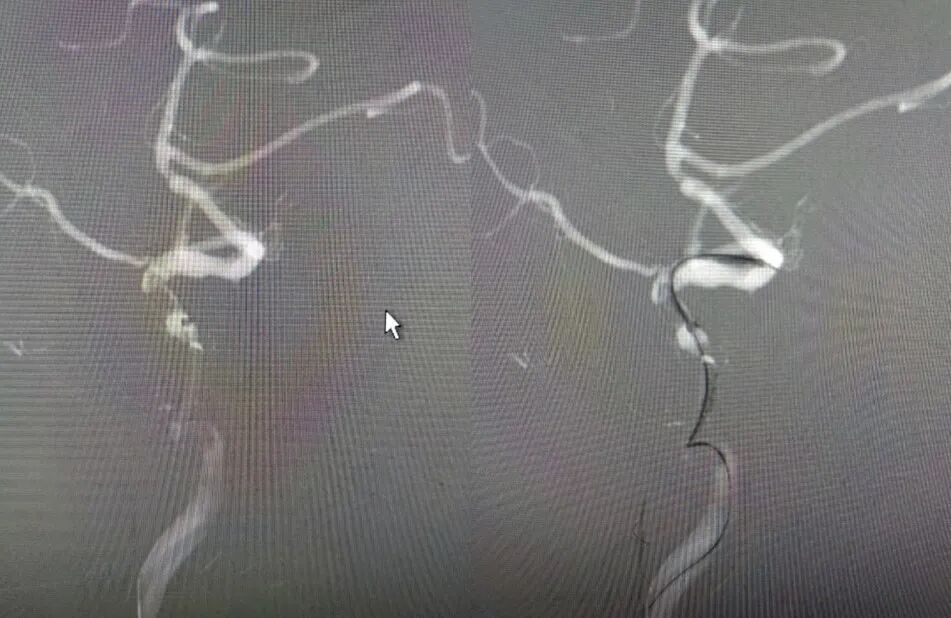

术后影像及检查

术后正位造影。

导丝怎么扩【载药时代 球扩天下】NOVA DES®颅内药物洗脱支架在大脑中动脉重度狭窄的应用二例!_https://www.jmylbn.com_新闻资讯_第30张

术后侧位造影

导丝怎么扩【载药时代 球扩天下】NOVA DES®颅内药物洗脱支架在大脑中动脉重度狭窄的应用二例!_https://www.jmylbn.com_新闻资讯_第31张